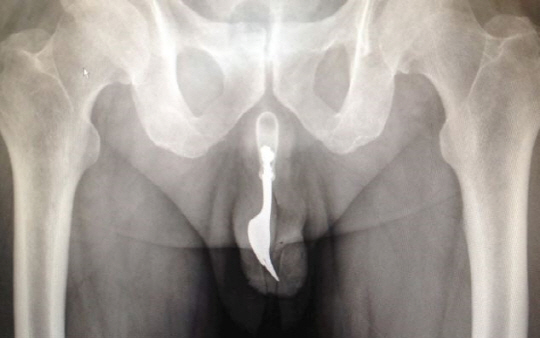

자신의 성기안에 쇠로 된 포크를 집어넣은 남성이 병원에서 수술을 받은 황당한 사건이 벌어졌다.

19일(현지시간) 영국매체 데일리메일에 따르면 호주 캔버라에 사는 70대 남성이 성적쾌감을 위해 10cm 길이의 포크를 요도안으로 집어 넣었다가 12시간동안 극심한 고통에 시달린 나머지 병원신세를 졌다.

의료진은 다량의 윤활제를 투입하고 핀셋으로 포크를 '무사히' 빼내는 데 성공했으며, 그 남성은 입원 치료없이 귀가했다.